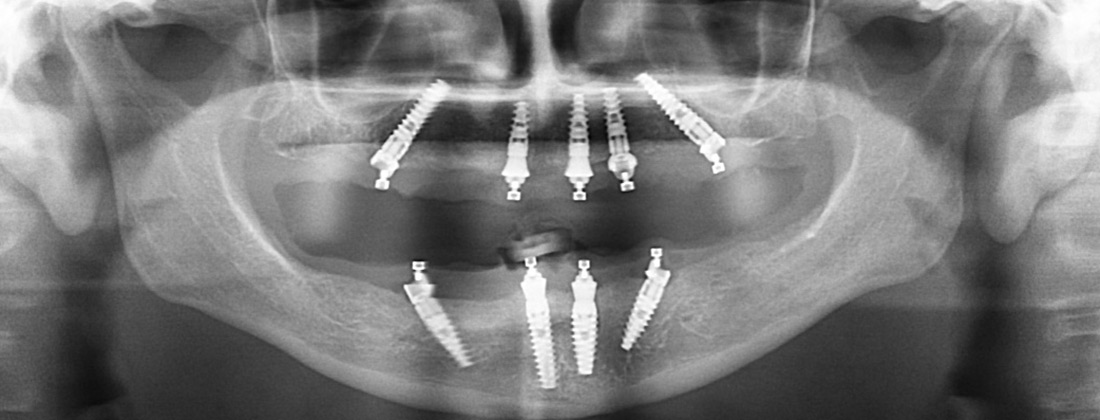

Fusion Dental Implant Club Redo All-on-X Case Example